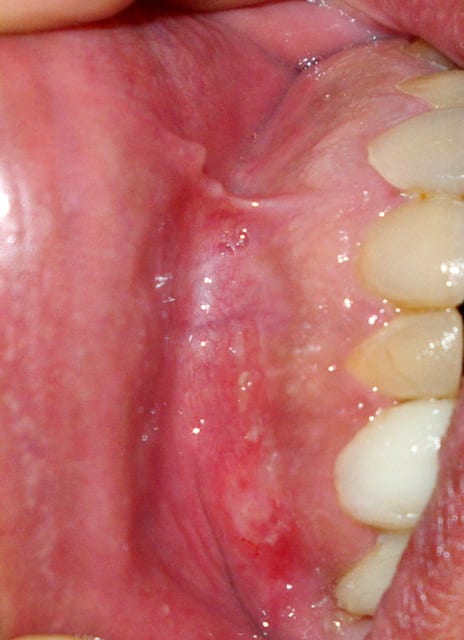

Le patient se plaint de douleurs gingivales en regard de la 13 depuis 24h. Elles sont permanentes, irradiantes, insomniantes et ne cèdent pas aux antalgiques. Elles s'accompagnent d'une altération de l'état général: grosse fatigue voire désorientation mais sans fièvre ni adénopathie.

La lésion semble bulleuse devenant érosive érythémateuse recouverte des lambeaux persistants blanchâtres du toit de la bulle. De taille environ 1cm de diamètre. Entourée au départ de petites bulles transparentes encore intactes.

J'ai revu le patient aujourd'hui, l'état général est amélioré mais les douleurs n'ont pas diminué limitant l'alimentation. La lésion ne semble plus être vésiculeuse, elle forme un placard blanchâtre sur un fond érythémateux mais le raclage est rendu difficile car très douloureux, je pensais à une candidose mais la couche blanchâtre ne semble pas s'éliminer et la lésion est isolée et ne semble pas s'étendre.

En même temps l'aspect me ferait bien penser à un lichen...